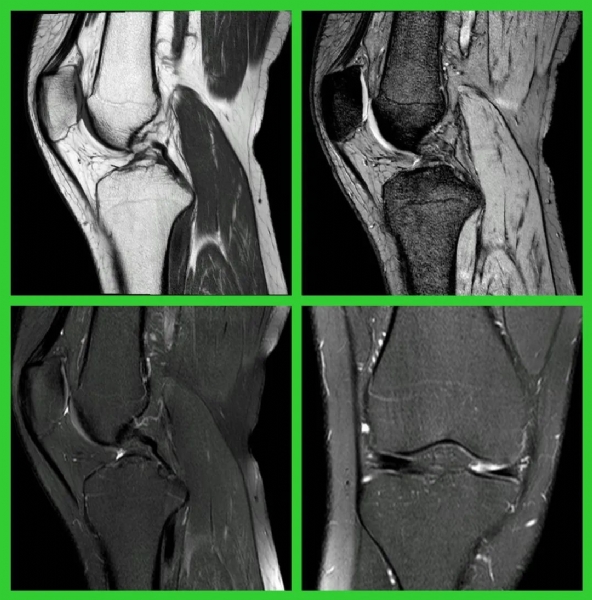

(前交叉韧带损伤的MRI表现)